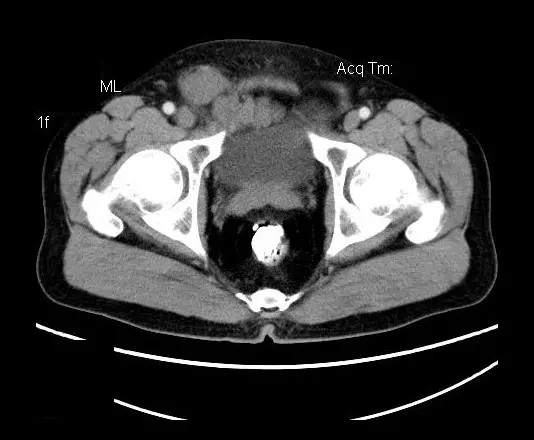

【影像表现】

盆腔右前侧及邻近腹股沟区可见多发大小不等的聚集生长的结节影,病灶呈软组织密度,边缘尚规整,分界尚清,增强扫描可见不均匀强化。膀胱局部受压,盆腔未见明显肿大淋巴结影。

盆腔神经鞘瘤的影像学表现主要取决于肿瘤本身细胞不同组成分布及排列(Antoni A区与B区不同比例)及肿瘤是否发生退变所致。Antoni A 区由密集的梭行细胞构成,细胞核排列为栅栏状或漩涡状。Antoni B区瘤细胞稀疏,网状排列,基质含水量高,常发生囊变或出血。

平扫影像表现:Antoni A区较多病灶,在CT上呈等或略高密度影,T1WI等信号、T2WI略高信号,AntoniB区较多病灶,CT多为水样低密度、T1WI低信号、T2WI明显高信号。

增强影像表现:神经鞘膜肿瘤增强后,由于Antoni A区与B区以不同比例混合而强化不一,呈不均匀斑片状,条状强化。Antoni A 区富血供,中等或明显强化,Antoni B区乏血供,强化多不明显。